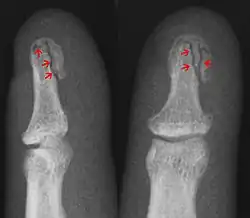

Die Diagnose wird durch ein Röntgenbild in zwei Ebenen gesichert, wie im Bild gezeigt.